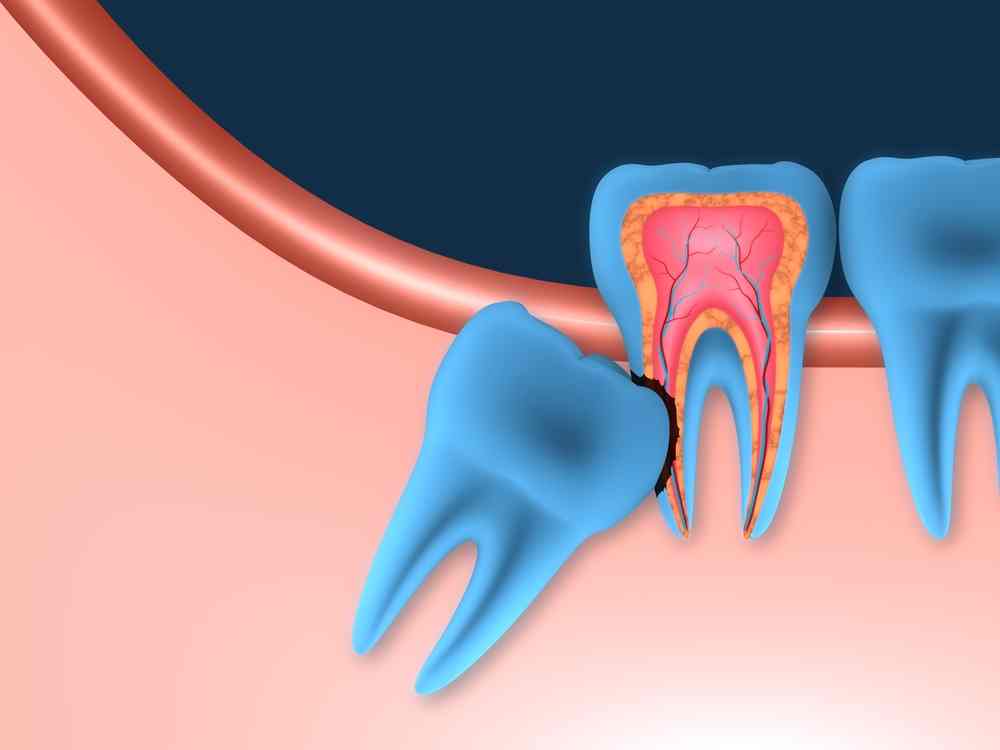

La aparición de las muelas del juicio puede provocar diversos problemas dentales. Debido a la falta de espacio en la mandíbula, las muelas del juicio pueden erupcionar parcial o completamente impactadas, es decir, que no pueden salir completamente de las encías.

Esto puede causar dolor, inflamación e infección. Además, las muelas del juicio también pueden ejercer presión sobre los dientes adyacentes, causando apiñamiento y desalineación dental.

Como resultado, muchas veces no hay suficiente espacio en la boca para que las muelas del juicio erupcionen correctamente. Esto puede causar que las muelas del juicio se impacten o queden atrapadas en el hueso o las encías, lo que puede ser doloroso e incluso causar infecciones.

Cuando las muelas del juicio no tienen suficiente espacio para salir, pueden quedar impactadas en la mandíbula o en las encías. Esto puede causar dolor, hinchazón, infecciones y daño a los dientes vecinos, lo que hace que la extracción sea necesaria en muchos casos. Las muelas del juicio impactadas también pueden causar la formación de quistes o tumores en el área afectada.

Dado que las muelas del juicio a menudo causan problemas dentales y no cumplen una función vital en la masticación, muchos dentistas recomiendan la extracción preventiva de estas muelas. La extracción temprana puede evitar complicaciones y reducir el riesgo de infecciones y daño dental. Además, la extracción de las muelas del juicio puede ser necesaria si se desarrollan problemas como caries, enfermedad de las encías o infecciones.